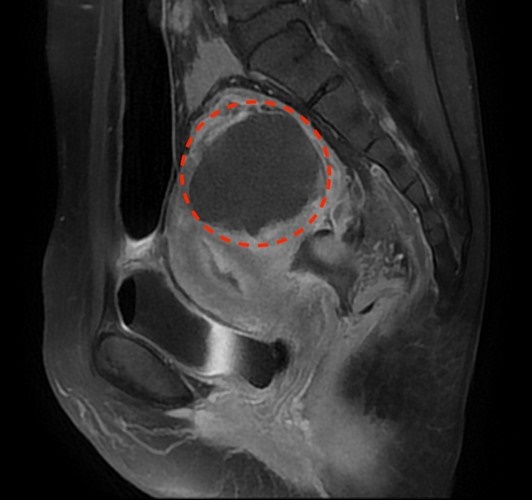

右圖:花蓮慈院婦科主任李佩蓁指出,一位子宮肌瘤合併右側卵巢巧克力囊腫的婦女,同步接受微波消融治療與摘除卵巢囊腫;經核磁共振造影掃描,子宮內的肌瘤已減少九成以上(紅圈所指),剩餘部分則會隨著時間萎縮。(李佩蓁提供)

花蓮慈濟醫院婦科手術中心繼引進無創標靶音波刀(MRgHIFU),再引進超微創微波消融刀最新技術,讓飽受子宮肌瘤、肌腺瘤等病苦的婦女有更多的治療選擇,婦科主任李佩蓁指出,一位患有6.5公分的子宮肌瘤合併右側卵巢5公分巧克力囊腫的45歲婦女,同步接受微波消融治療與摘除卵巢囊腫;整個消融過程僅19分鐘11秒,且經核磁共振造影掃描,子宮內的肌瘤已減少九成以上,剩餘部分則會隨著時間萎縮。